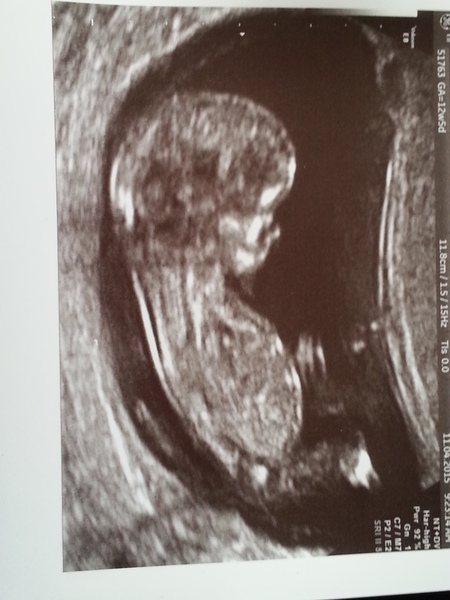

I had the 12 week scan early this morning and all went well! I've hopefully included a pic - Bubba is 6cm and appears to have a big fat head and belly. They've estimated that it's 12+3 but I'm still convinced that it's 12w exactly due to my irregular periods. The nuchal measurement was 1.5mm (normal) but I'll get a phone call in a few days if I'm deemed to be high risk based on the blood test. If I don't hear anything from them by next weekend then I'll assume it ok to tell people.